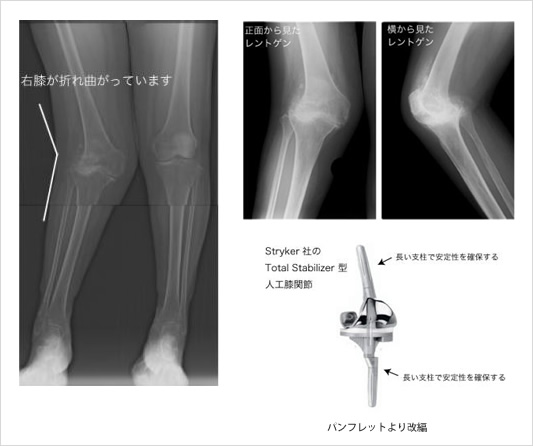

リウマチ性膝関節症│リウマチ・関節センター【整形外科部門】|診療科